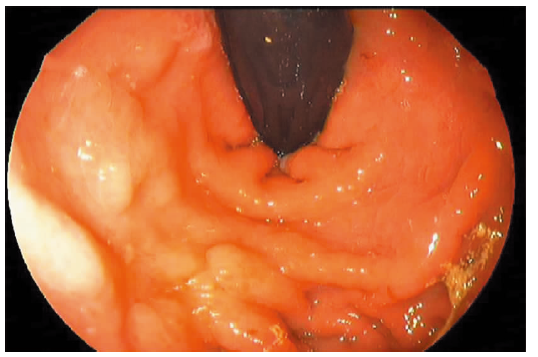

摘要:目的分析和随访内镜下组织黏合剂联合硬化剂注射治疗门静脉高压症胃静脉曲张的疗效及预后。方法研究纳入2006年至2015年期间84例上消化道出血,胃镜检查显示胃静脉曲张,行内镜下组织黏合剂联合硬化剂注射治疗的病人,比较治疗前后出血频率,随访胃静脉曲张消除率及疾病转归。结果84例病人内镜治疗共111例次,平均治疗(1.32±0.68)次/例。内镜治疗前出血(0.72±0.54)次/月,治疗后出血(0.30±0.82)次/月,两者比较差异有统计学意义(P<0.01)。内镜治疗后6个月内胃静脉曲张根除(基本消失)率为75.0%,治疗6个月后为70.8%。术后随访(14.82±19.30)个月内未发生再出血,术后无异位栓塞与感染并发症发生。结论内镜下组织黏合剂联合硬化剂注射治疗有效降低胃静脉曲张出血频率,改善曲张静脉状态,是预防胃静脉曲张再出血的重要方法之一,可在临床应用推广。

Abstract:ObjectiveTo analyze the therapeutic effect of endoscopic injection of tissue adhesive combined with hardener for the portal hypertensive patients with gastric varicose and prognosis.MethodsA total of 84 patients with upper gastrointestinal hemorrhage and gastric varices diagnosed by gastroscopy during 2006 to 2015, who were performed endoscopic injection with tissue adhesive with hardener, were included in this study. The rate of gastric hemorrhage was compared before and after endoscopic treatment. The rate of gastric varices elimination and the prognosis were analyzed.ResultsThere were 111 times of endoscopic treatment for 84 cases with an average of(1.32±0.68) times per case. Bleeding was (0.72±0.54) times/month before treatment and (0.30±0.82) times/month after treatment respectively with significant difference statistically(P<0.01). The eradication rate of varicose veins with almost disappearance was 75.0% during the period of 6 months post endoscopic treatment and 70.8% after 6 months of endoscopic treatment. No re-bleeding was found without any complications, ectopic embolization and infection after follow-up of (14.82±19.30) months.ConclusionsEndosco-pic injection of tissue adhesive and hardener for gastric varices would reduce the rate of bleeding of gastric varicose and the varicose vein, which was an important procedure for prevention of re-bleeding of gastric varicose vein and could be applied clinically.